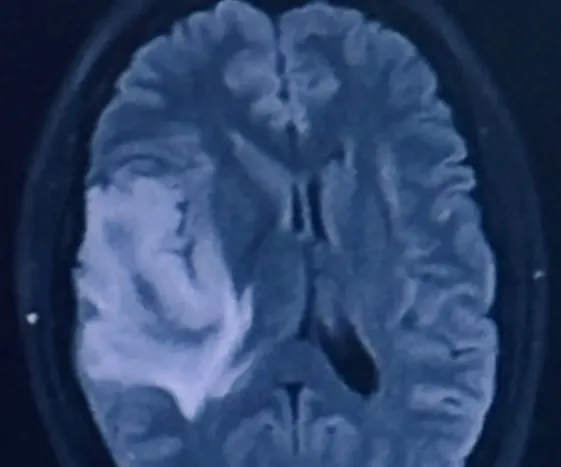

收藏女子偏头痛+脸发麻,突然癫痫昏迷后才查出脑癌!这些症状可千万别忽视啊…